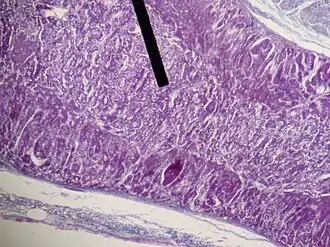

Adrenal medulla (on the pointer) stains lighter than the adrenal cortex, H&E stain